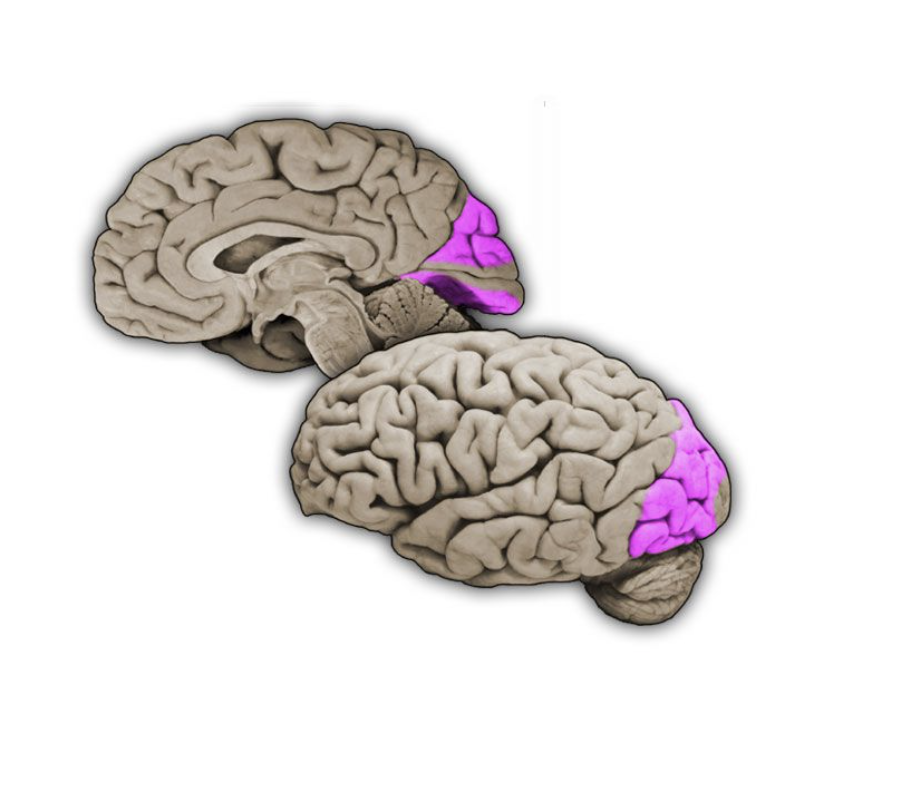

Parietal lobe

Region of the cerebral cortex posterior to the central sulcus, anterior to the occipital lobe and superior to the lateral fissure; involved in somatic sensation and numerous complex functions, including multimodal proprioception, language comprehension, attention, and spatial awareness.

Postcentral gyrus

Vertically oriented gyrus that forms the posterior bank of the central sulcus; this gyrus contains the primary somatosensory cortex.

Primary somatic sensory cortex

Cortical areas (Brodmann's areas 3, 1 and 2) in the postcentral gyrus that first receive somatosensory signals from the relevant thalamic nuclei (ventral posterior complex). Also called primary “somatosensory” cortex.